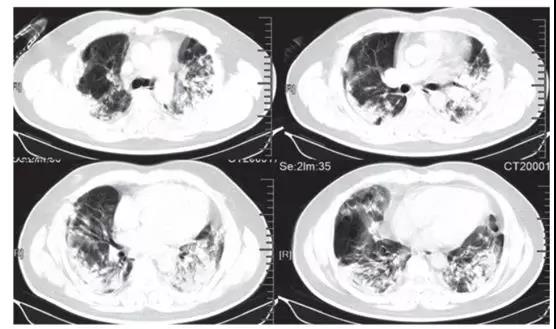

随后的胸部CT显示双侧毛玻璃样混浊,而实变消除(见下图)。